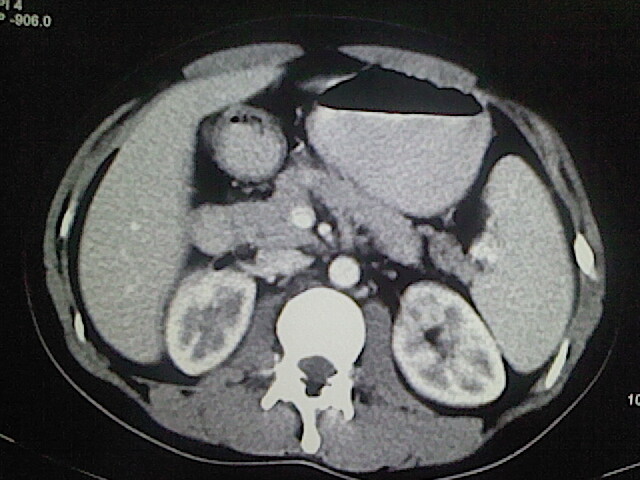

以下是引用卜一在2009-3-14 9:49:00的发言:[br]胆囊萎缩,胆囊壁不规则增厚,内部结构模糊,增强明显强化。另:肝左叶外侧段肝囊肿。支持:慢性胆囊炎!高度可疑:胆囊癌!

以下是引用余辉在2009-3-14 8:48:00的发言:[br]1)慢性胆囊炎。2)肝左叶外侧段肝囊肿。3)脂肪肝。[br]支持,胆囊萎缩,密度增高,不知b超具体有何提示,钙胆汁?结石?

以下是引用jiangjing在2009-3-14 10:18:00的发言:[br]1)慢性胆囊炎。2)肝左叶外侧段肝囊肿。3)脂肪肝。4.】建议行肝功能检查